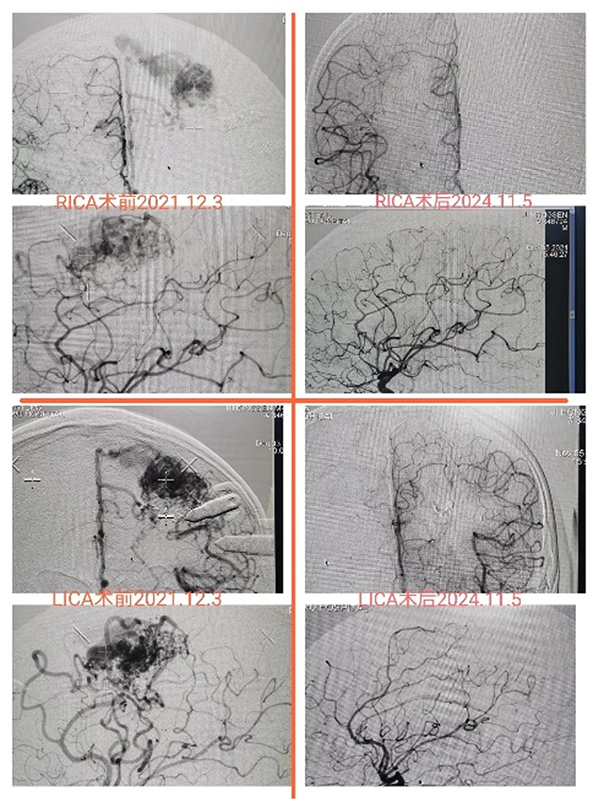

在脑动静脉畸形方面,完成了超过700例患者的治疗,全部采用“DSA+MR双定位”技术;联精准定位畸形团,最大程度保护引流静脉和脑组织结构;此外,我们创新性采用“伽玛刀+介入栓塞同期治疗脑动静脉畸形”技术,有效降低了患者术后出血风险,改善患者预后,减少射线相关损伤。

图:48岁,男性,反复癫痫起病,栓塞后半年行单次伽玛刀治疗,术后3-年造影证实畸形完全闭塞